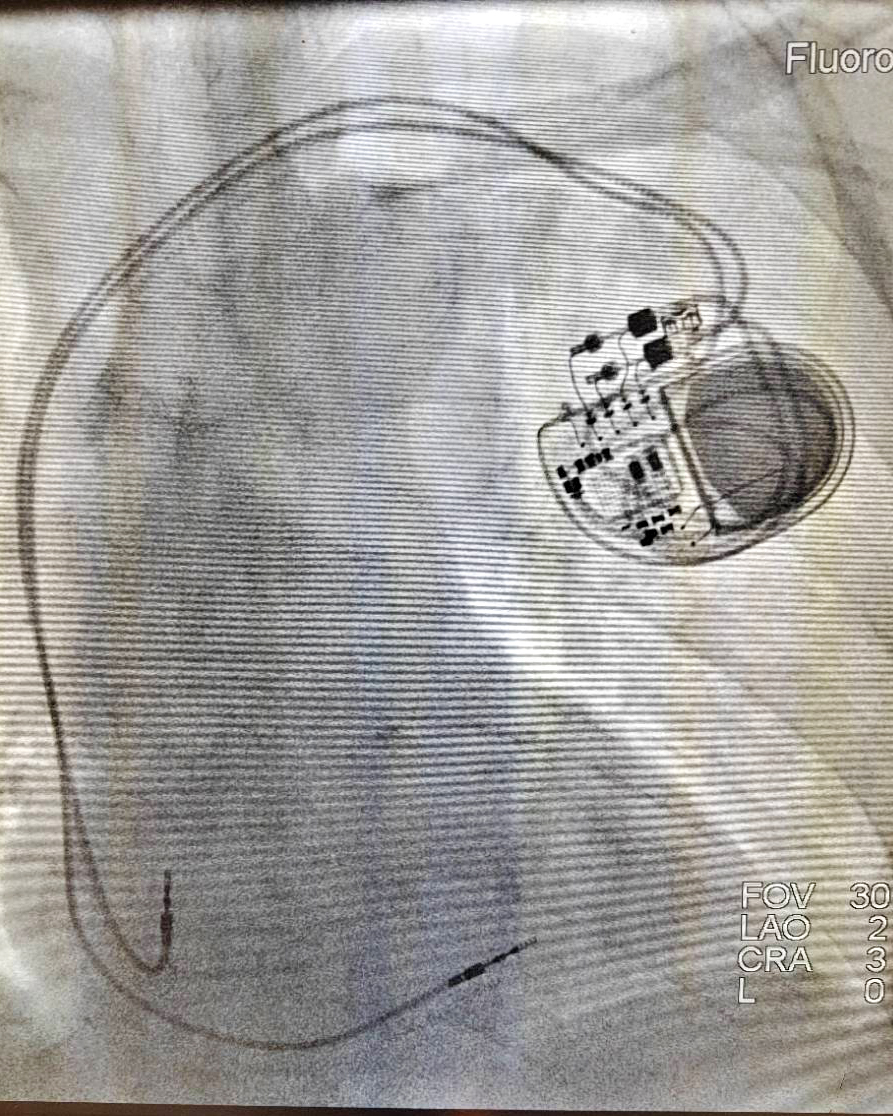

9月16日,宣汉县人民医院介入科团队为一名“三度房室传导阻滞”老年患者成功植入抗核磁共振起搏器,这也是全县首例抗核磁共振起搏器植入手术。

患者是一名老年女性。经多次行动态心电图检查明确为间歇性三度房室传导阻滞。心内科医生考虑患者病情及年龄大等多因素,以后可能还需经常做脑血管核磁等检查,与患者家属沟通后,建议植入抗核磁共振永久性起搏器。

抗核磁共振起搏器在患者进入磁场检查室时可以感知磁场,在10秒内自动转换为抗核磁模式,检查结束离开核磁室后,起搏器自动恢复为日常起搏模式,这样抗核磁模式时间可缩至最短,确保患者最佳效果。目前,患者术后效果良好。